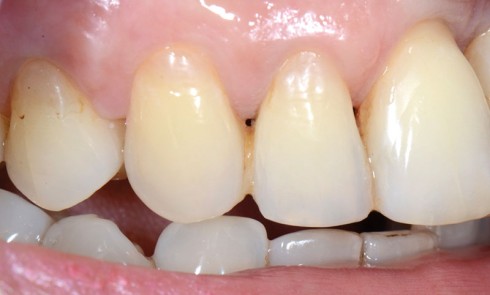

Article réservé à nos abonnés La prothèse composite dans la gestion esthétique et biomécanique d’un édentement unilatéral de grande étendue

La réhabilitation des édentements terminaux unilatéraux de grande étendue par prothèse amovible partielle métallique (PAPIM) conventionnelle pose plusieurs problèmes essentiellement...